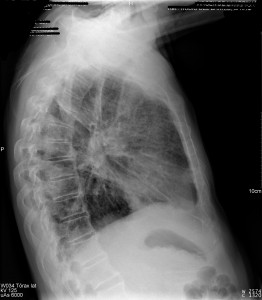

En efecto, la radiografía de tórax en proyecciones PA y lateral es la técnica de elección. La radiografía de tórax es el estudio inicial a realizar en todos los pacientes con sospecha de enfermedades respiratorias. Además, es una prueba muy accesible, de bajo coste e ideal para orientar el diagnóstico en este caso.

Un mes después tenemos las siguientes imágenes radiológicas: